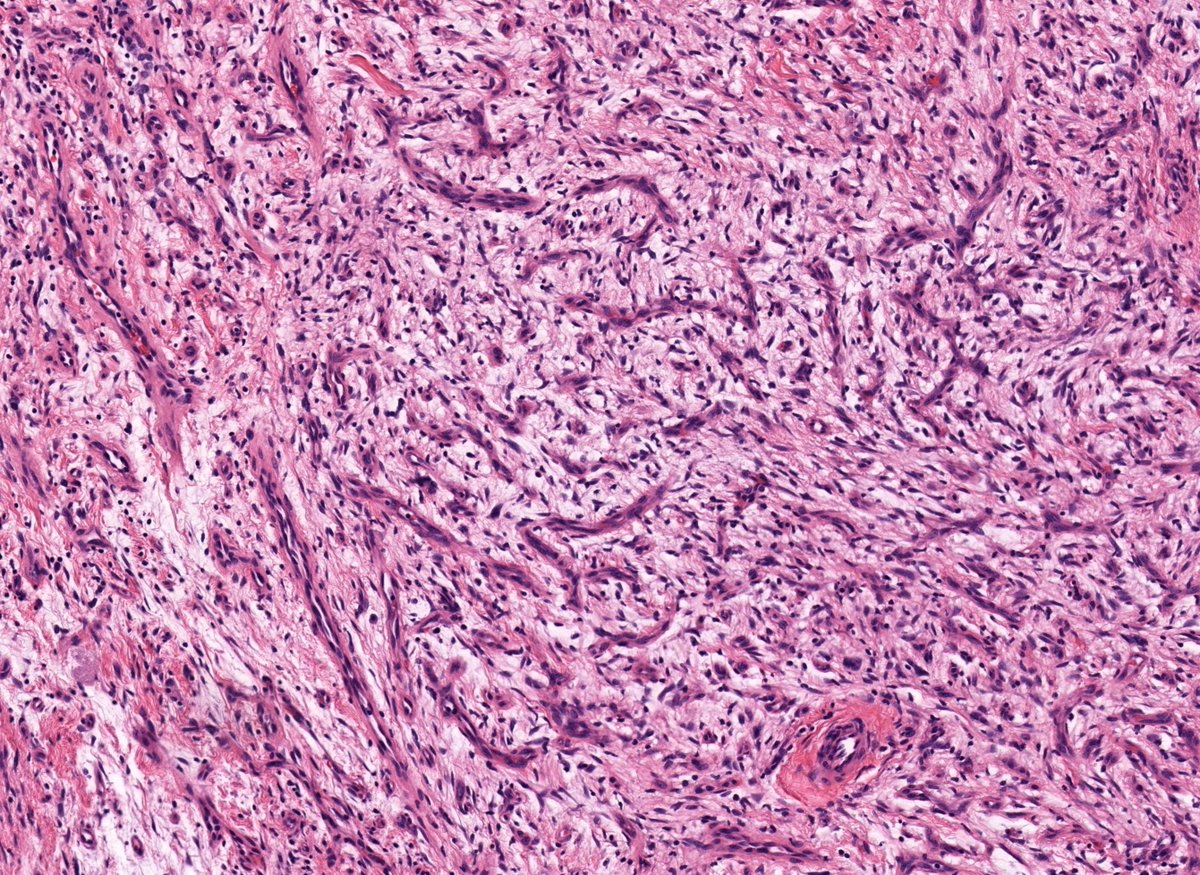

20 yo M. Deep intramuscular calf nodule. SOX-10 +. Loss of SMARCB1 staining. Answer ✅ youtu.be/YrUty8brYHU?si… Digital slides: kikoxp.com/posts/21930 #pathology #pathologists #pathTwitter #dermpath #dermatology #dermatologia #dermtwitter #BSTpath

20 yo M. Deep intramuscular calf nodule. SOX-10 +. Loss of SMARCB1 staining.

Answer ✅ youtu.be/YrUty8brYHU?si…

Digital slides: kikoxp.com/posts/21930